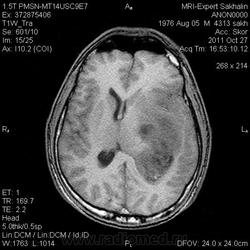

Помогите разобраться!Образование головного мозга.

Мужчина без направления.Жалобы на потерю памяти,шум в ушах в течение последнего года.

Заподозрила образование  из сосудистого сплетения заднего рога бокового желудочка  .Смещение срединных структур.Здесь отек смешанного типа?

Вряд ли это из желудочка, височный рог (кажется) виден на одном из сканов, он не расширен. Скорее всего глиальная опухоль. А то, что выглядит как асширенные сосуды - скорее всего кистозные полости.

Вы правы, я затупила- смторела на  flaer , а думала о Т2 , конечно  же это никакие не сосуды , а кистозные полости.

Не характерный тип накопления при эпиндимоме (если подозреваете желудочек),  и тем более для сосудистой неоплазии, к тому же слишком большой мягкотканный компонент.

Отсутсвие накопления  позволяет предположить глиальную опухоль высокой степени дифференцировки.

Справедливости ради, нужно отметить необычность наблюдения, а именно эти преусловутые кисты. Что это за кисты, каков их патогенез? На аксиальных сканах выглядит как длинная тонкая исчерченность.  В результате некроза?  99% что нет. Похожи или на аксональную дегенерацию или сосуды. Я склоняюсь ко второму, быть может оборвавшийся неоангиогенез, слепо заканчивающиеся зачатки патологического сосудистого русла,  со сверхнизким кровотоком.  Хотя это не укладывается в высокодифференцированную опухоль.

Согласен с Евгением. Больше похожа на анапластическу глиому - астроцитому или олигодендроглиому. У глиобластомы, как правило, преобладает кистозный компонент.

С трудом представляю механизм развития некроза, который приведет  к подобной картине. Длинная исчерченность в одном направлении. Что может привести к формированию подобных полостей с сохранными стенками?   Получается, здесь некроз есть, здесь некроза нет, здесь опять есть и так много раз на протяжении ~5 см ?.. слишком уж структурно. Некроз в опухоли возникает из-за нарушения трофики, т.е. питающие сосуды в силу своего нео-патологического роста не обеспечивают необходимый обьем кровотока. Предполагая, что каждый сосуд питает плюс-минус сферическую область - находим это подтверждение во всех образованиях с периферическим типом накопления. Некроз сьедает все. Подобную избирательность в виде макарон с центральным каналом :) можно обьяснить, ну, наверное, только на уровне капилляров. И все равно понять подобное 1-2мм -чередование "полость-стенка" затруднительно.   Даже если это и не "макароны"  (хотя на аксиальных они выглядят именно так),  не забываем, что и без того в самой по себе  безструктурной опухоли естественный некроз вызывает вообще полный хаос. Если где-то в этой зоне интереса определялись бы привычные нам рваные некротические полости, чередующиеся маленькими - тогда более менее понятно.

Передумал, под аргументрованными высказываниями мудрых товарищей - глиома или астроцитома...